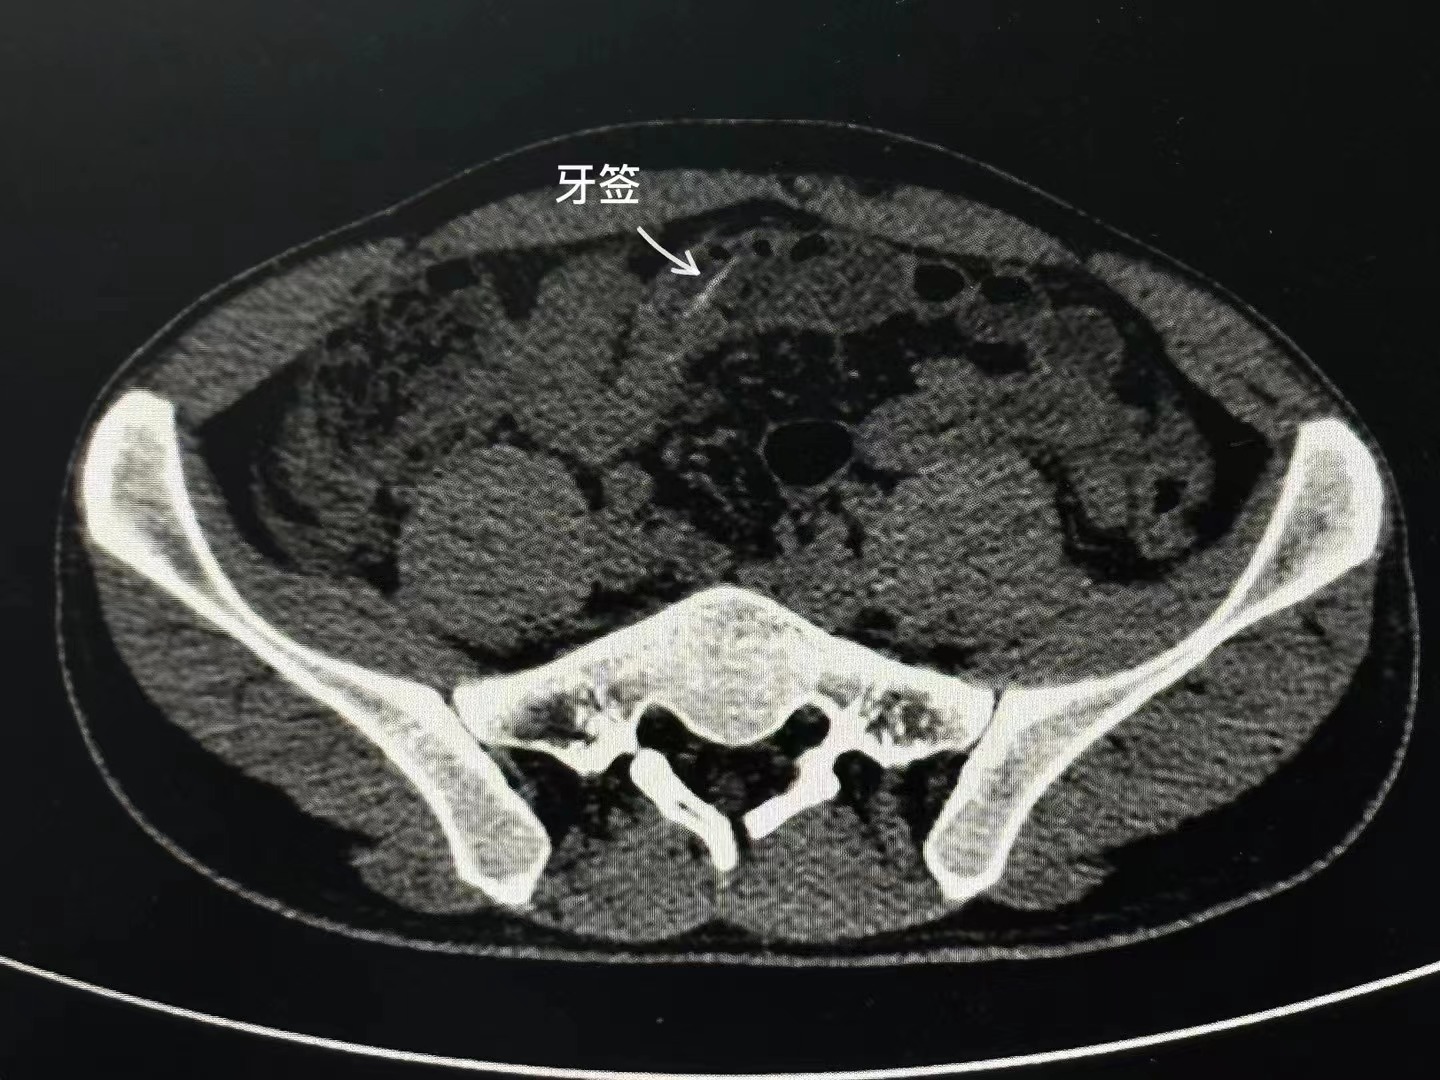

柳州市人民医院急诊科的医生接诊了小张。经复查CT,医生在小张的肠道内看到一根异物。凭借多年的诊疗经验,医生初步判断异物为牙签。

异物刺穿小肠,与术前CT阅片结果一致。医生术中诊断小张为消化道穿孔、急性弥漫性腹膜炎和小肠内异物。随后,医生在腹腔镜下操作,完整地将牙签从患者的肠腔内取出,然后做缝合修补小肠等处理。经过两个多小时,手术顺利完成。患者术后返回病房看到异物,心有余悸。